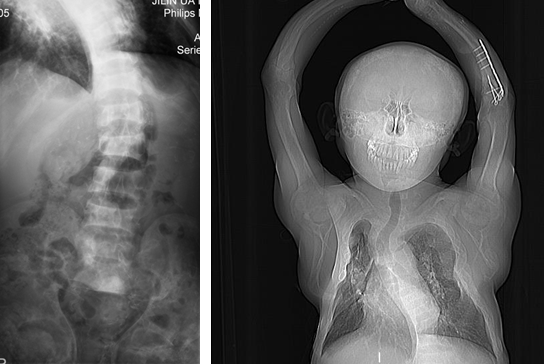

据了解,患者是一名29岁的男性,已透析治疗11年,2年前发生继发性甲状旁腺功能亢进(SHPT),1年前骨痛逐渐加重,行走困难,面部变形,上颌肿大,鼻子扁平,凹陷变宽,面部呈现“狮面症”。由于上下颌增大,患者出现了严重的口齿不清,随后出现呼吸困难。此外,患者全身骨骼也出现严重变化,身高降低、脊柱畸形、四肢畸形,这使患者行走困难。日夜持续的骨痛、呼吸困难和长期卧床严重影响了患者的生活质量。

该患者到我院就诊时,张弘教授接诊了该患者,并启动MDT为患者制定个体化治疗方案。术前患者甲状旁腺激素(iPTH)水平为2000 pg/mL,血钙2.49 mmol/L,血磷2.44 mmol/L。彩超提示甲状旁腺区见4个低回声、边界清楚、部分微钙化的结节,提示双侧甲状旁腺增生。99mTc-MIBI甲状旁腺双时像显像准确定位了3个增大的甲状旁腺。结合核医学科和超声科的精准定位,患者SHPT诊断明确。

患者基础疾病较多、营养状况差,麻醉科高度重视,潘振祥主任亲自主持会诊,严密制定麻醉和应急方案。在麻醉科的紧密配合下,张弘教授为患者进行手术治疗,术中发现四枚增大的甲状旁腺并全部切除,术中病理证实其均为增生的甲状旁腺组织。术后患者拔管清醒抵达ICU,观察一夜病情稳定。术后第1天,患者的骨痛症状“神奇”地消失了。随后,患者安返肾病内科病房,经过肾病内科的精细治疗,患者已可离床活动,顺利出院。至此,一场以病人为中心的多学科治疗顺利完成。在术后随访的1年中,患者恢复良好。